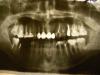

andrez Опубликовано 4 февраля, 2011 Поделиться Опубликовано 4 февраля, 2011 Здравствуйте !Следующая проблема с зубами:Время от времени(особенно когда застужу) возникает несильная, но постоянно ноющая боль в зубах. Практически все зубы депульпированы.Это продолжается от нескольких дней до нескольких недель(время от времени затухая) причем в разных местах от левой четвертки(рядом с временной одиночной коронкой на панорамном снимке) до правой тройки вверху и от левой четвертки до правой четверки внизу.После панорамного снимка, удалил нерв в левой семерке(снимок 7l) и в правой четверке (снимок 4r), а также переделал правую семерку(7r)(все - нижняя челюсть). Улучшение не случилось.Стоматолог посоветовал обратится к неврологу, что я и собираюсь сделать в ближайшее время, но хочется быть уверенным, что со стороны стоматологии все сделано.Еще один вопрос по нижней правой семерке: на панорамном снимке показывается, что один канал не запломбирован(этот зуб делал очень давно и он не беспокоил). При попытке его переделать, до конца пройти не удалось(снимок 7r). Врач сказала, что скорее всего его пломбировали "не контрастным материалом", который раньше применялся. Теперь вопрос: надо ли его пытаться еще раз перепломбировать у другого врача( я собираюсь на него мост крепить).Спасибо.Андрей З.Москва Ссылка на комментарий

andrez Опубликовано 8 февраля, 2011 Автор Поделиться Опубликовано 8 февраля, 2011 Подскажите, пожалуйста по 44 и 47 зубам(два нижних снимка). Надо их перелечивать? Ссылка на комментарий

juli63 Опубликовано 8 февраля, 2011 Поделиться Опубликовано 8 февраля, 2011 но хочется быть уверенным, что со стороны стоматологии все сделано. Теперь вопрос: надо ли его пытаться еще раз перепломбировать у другого врача( я собираюсь на него мост крепить). хотите быть уверены-сделайте компьютерную томографию челюсти. если вы любите экстрим-крепите мост. я бы не рискнула. а то что осталось от 6 зуба никого не смутило. там тоже проблема имеется, а у 4 похоже 2 корня и/или 2 канала. Ссылка на комментарий